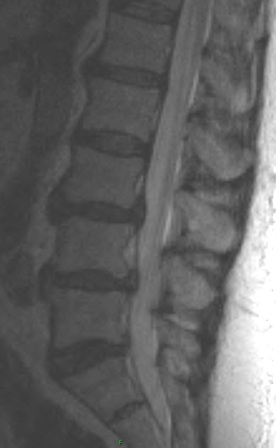

There is evidence of a grade 1 anterolisthesis of L3 on L4. The second set of images show non acute bilateral pars fractures at L3, responsible for the anterolisthesis.

The patient has an isthmic spondylolisthesis of L3. This is a unique case in that L5 is by far the most common location for this type of spondylolisthesis, with L4 less common, and L3 even more uncommon.